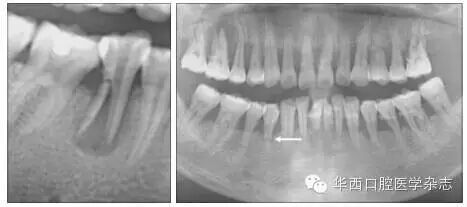

牙根折裂好发于下颌第一磨牙的近中根及上颌第一磨牙的近颊根、腭根,也可见于第二磨牙、前磨牙等(图12)。可以单发,也可对称性多发(图3)。可以是双侧的同名牙,也可以是同侧的上、下颌同名牙或相邻牙(图45)。

左:36牙近中根管下段内径增宽;右:36牙折线明显,折片向近中移位,伴牙槽骨吸收。

1 36牙近中根牙根折裂

左:45牙根纵行折裂,折片向远中移位;右:44牙根横行折裂(箭头示),全口牙槽骨重度吸收。

2 下颌前磨牙牙根折裂

36牙近中根见根管下段扩大、伴牙周膜间隙增宽以及根尖周骨质吸收;46牙近中根折裂,折片移位。

3 双侧下颌第一磨牙对称性牙根折裂